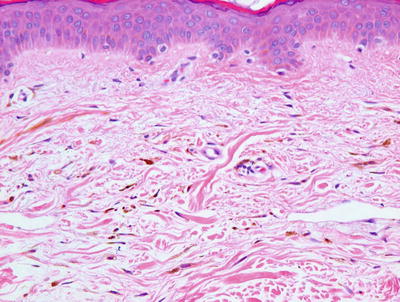

Lentigo simplex is characterized by orthokeratotic keratin overlying an epidermis with elongated rete ridges. There is increased melanin within basilar keratinocytes (Fig. 20.1). Melanocytes are minimally increased in number, and they are not atypical [2]. There is no nesting of melanocytes as seen in a junctional nevus. The dermis is unremarkable. Specifically, it is distinctly unusual for a lentigo simplex to induce a significant inflammatory response or upper dermal fibrosis. The presence of such changes warrants careful examination to exclude histologic mimics.

Fig. 20.1

Lentigo simplex has elongated rete ridges and increased basilar melanin . There are essentially normal numbers of melanocytes present in the epidermis. Sun damage is not present in the underlying dermis